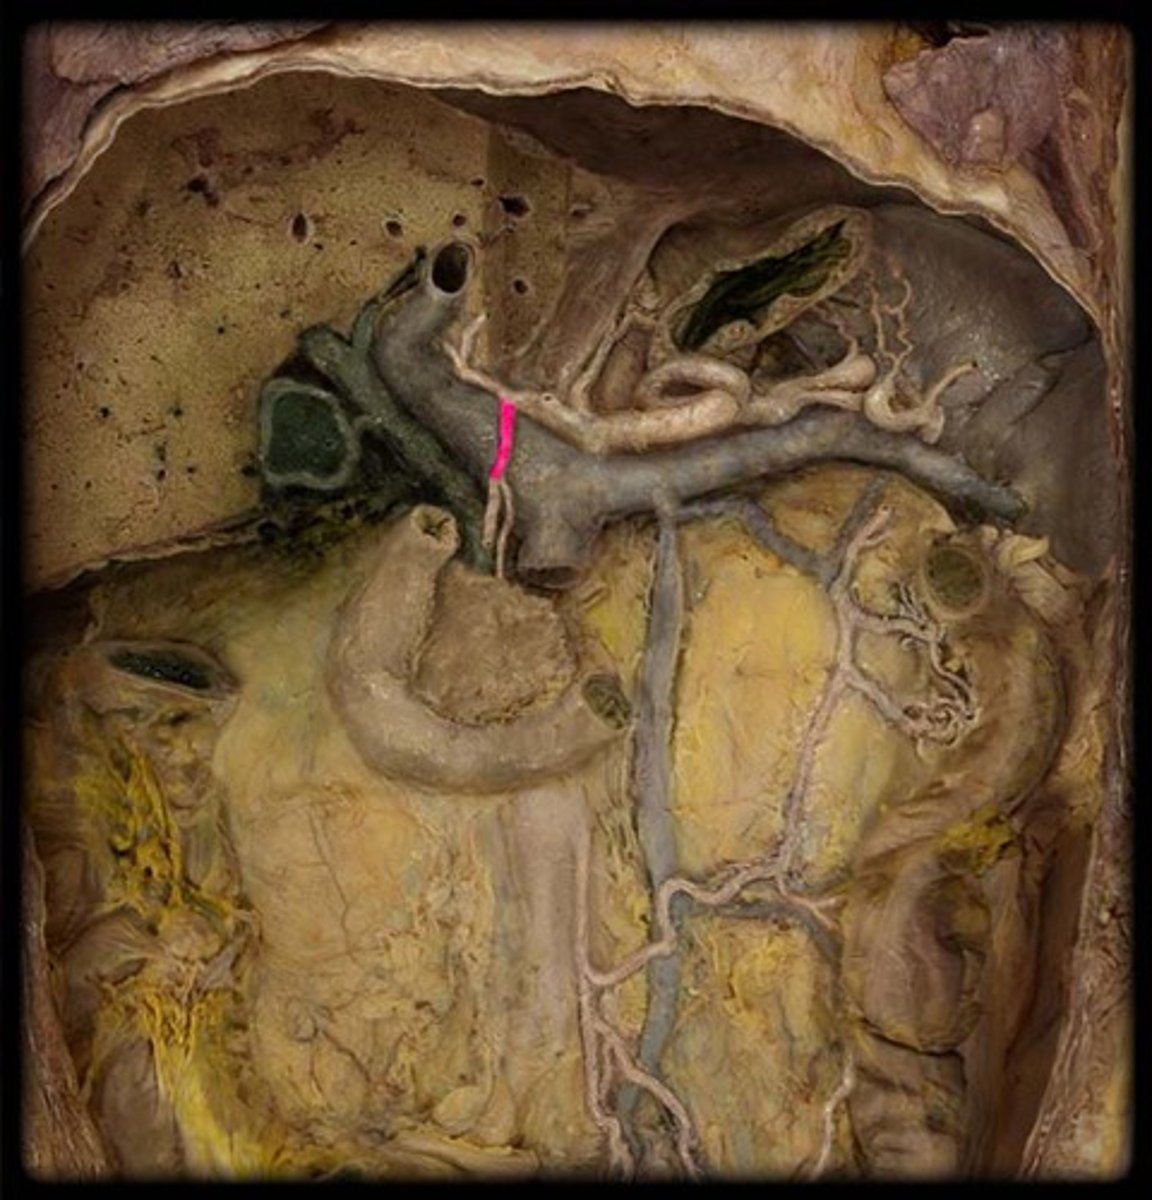

portal triad

what is in this structure

hepatic artery proper

common bile duct

common hepatic duct

cystic duct

hepatic portal vein